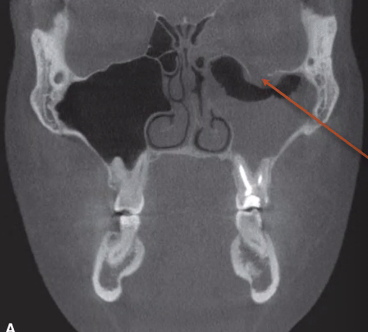

orbital blowout fracture

look for “trap door”

inferior orbit breaks because it is the weakest

zygomatic fracture

injury on patient’s left